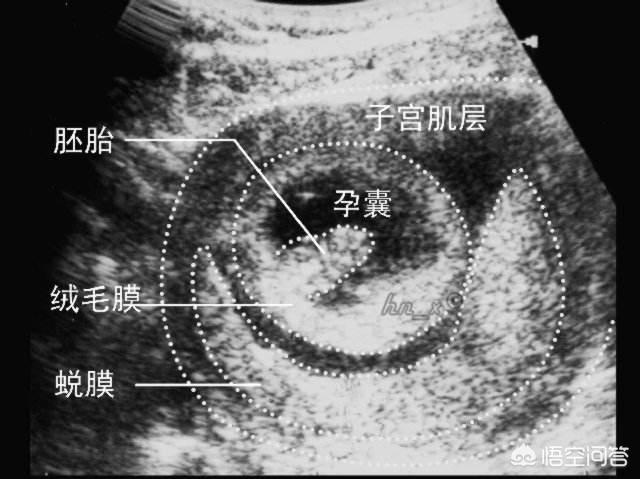

怀孕4周时,受精卵才着床成功; 怀孕5周时,受精卵着床成功后一边快速进行细胞分裂,一边向四周扩展,而这些细胞将会形成羊膜和血管包裹住 卵黄囊,胎儿就是从卵黄囊开始发育的。 在卵黄囊的外面是孕囊,孕囊是原始的胎盘组织。 所以, 一般在怀孕56周,可以做B超看到孕囊和卵黄囊,月经规律的女性,最早在怀孕35天时可以通过阴超看到孕囊; 怀孕67周时,可以通过B超看到胎3 怀孕5周孕囊大小多少是正常的 1、4周:胎儿只有02厘米。 受精卵刚完成着床,羊膜腔才形成,体积很小。 超声还看不清妊娠迹象。 2、5周:胎儿长到04厘米,进入了胚胎期,羊膜腔扩大,原始心血管出现,可有搏动。 B超可看见小胎囊,胎囊约占宫腔不到1胎芽特征 怀孕的第一个月为胎芽期,新生命在此期的成长速度是其一生中最快的。 妊娠第二周末精卵结合,受精后约4天,分裂成细胞团的精卵沿着 输卵管 到达子宫。 第三周,细胞团脱去外膜,为着床作准备。 第四周,胚泡已牢固地植入子宫里。 在这个